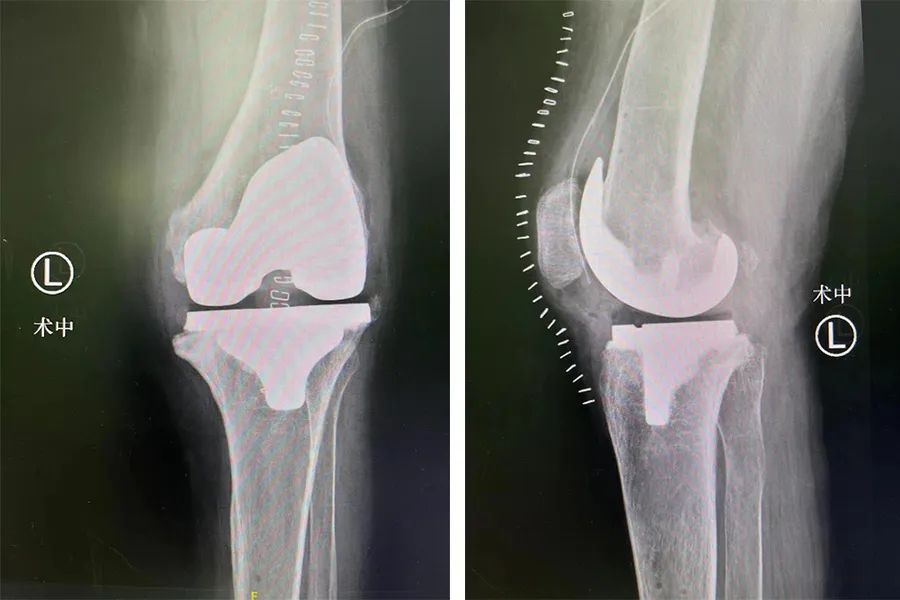

在结合相关资料及术前讨论后,仁慈关节外科张传开、郝亮、王琳、蒋涛手术团队为李大姐在 Mako 关节置换机器人导航下行左侧人工膝关节置换术。

术前,Mako 机器人基于 CT 进行 3D 的智能建模,根据患者实际情况个性化定制手术方案。同时,在术中实时根据患者具体软组织张力进行动态调整,辅助手术医生进行精准化、个性化的手术操作。尤其是对截骨、假体安装等重要环节,都进行了全程三维定位,实时将角度、大小、骨质覆盖等重要信息通过数字影像及时传达给手术医生,帮助医生做出准确判断,将手术精度控制在毫米级,实现「精准手术」的要求。

与传统骨科手术相比,Mako 机器人能够辅助手术医生准确快速地完成假体植入,其精准度远超传统术式,解决了手术医生「看不准」、「拿不稳」的问题。